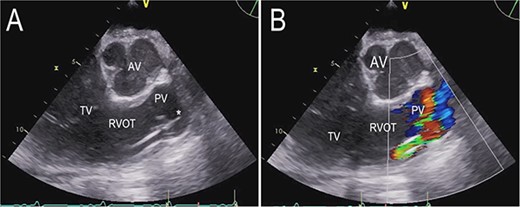

The transthoracic echocardiogram revealed severe dilatation of the left ventricle with a left ventricular end-diastolic diameter of 7.4 cm and a left ventricular systolic function of 15–20% (using Simpson’s biplane method of disks). The size of the right ventricle was normal. The right ventricular systolic function was mildly reduced by visual estimation. There was moderate to severe mitral regurgitation. The aortic valve was normal. The pulmonary and tricuspid valves showed trivial regurgitation (Fig. 1, Video S1 in the Supplementary Material online).

Transthoracic echocardiogram before LVAD implantation. Parasternal short-axis view. AV (aortic valve), LA (left atrium), PV (pulmonary valve), RA (right atrium), RVOT (right ventricular outflow tract), TV (tricuspid valve).